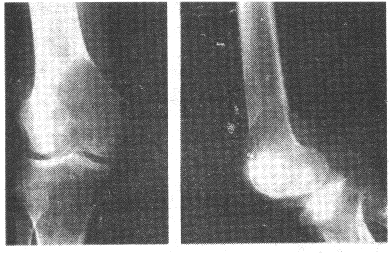

3.女性,19歲,右股骨下端疼痛3個月。X線片如圖。診斷應(yīng)考慮

正確答案:A 解題思路:骨肉瘤主要成分為腫瘤性成骨細胞、腫瘤性骨樣組織、腫瘤骨,還可見到腫瘤性軟骨組織和纖維組織。

4.男,17歲。右膝關(guān)節(jié)疼痛1個月余,輕度腫脹。X線片示脛骨近端圓形骨質(zhì)破壞(如圖),應(yīng)考慮的診斷是

正確答案:C 解題思路:骨結(jié)核大多數(shù)繼發(fā)于肺結(jié)核。結(jié)核桿菌經(jīng)血行到達骨或關(guān)節(jié),停留于血管豐富的骨松質(zhì)內(nèi)而發(fā)病,病理上表現(xiàn)為滲出、變質(zhì)和增殖。